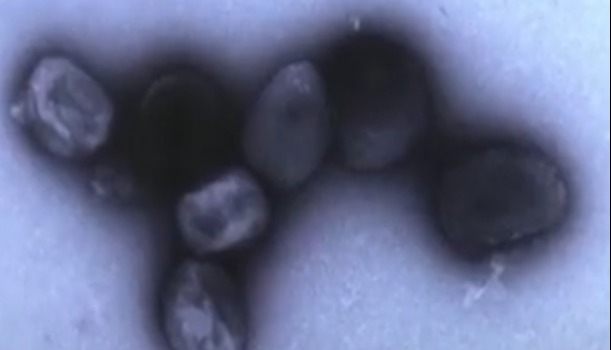

資料圖為世界衛生組織總部外景 來源:新華社 世衛組織說,此次疫情發生在剛果(金)赤道省。當地衛生部門今年1月和2月分別在該省的博隆巴和巴桑庫蘇地區發現病情。目前上述兩個地區共報告1096例病例,死亡病例增至60例。患者的症狀包括發燒、頭痛、肌肉和關節疼痛、頸部僵硬、咳嗽、嘔吐、腹瀉等,部分病患還出現鼻出血症狀。 世衛組織表示,初步實驗室檢測已排除埃博拉病毒和馬爾堡病毒,約半數樣本檢測呈瘧疾陽性。剛果(金)衛生部門和世衛組織正在對不明原因疾病進行進一步調查。 世界衛生組織在報告中指出,“偏遠的地理位置和薄弱的醫療基礎設施增加了疾病進一步傳播的風險。” 目前,當地衛生官員正與世界衛生組織合作進行調查。(完) 【編輯:林曉惠】